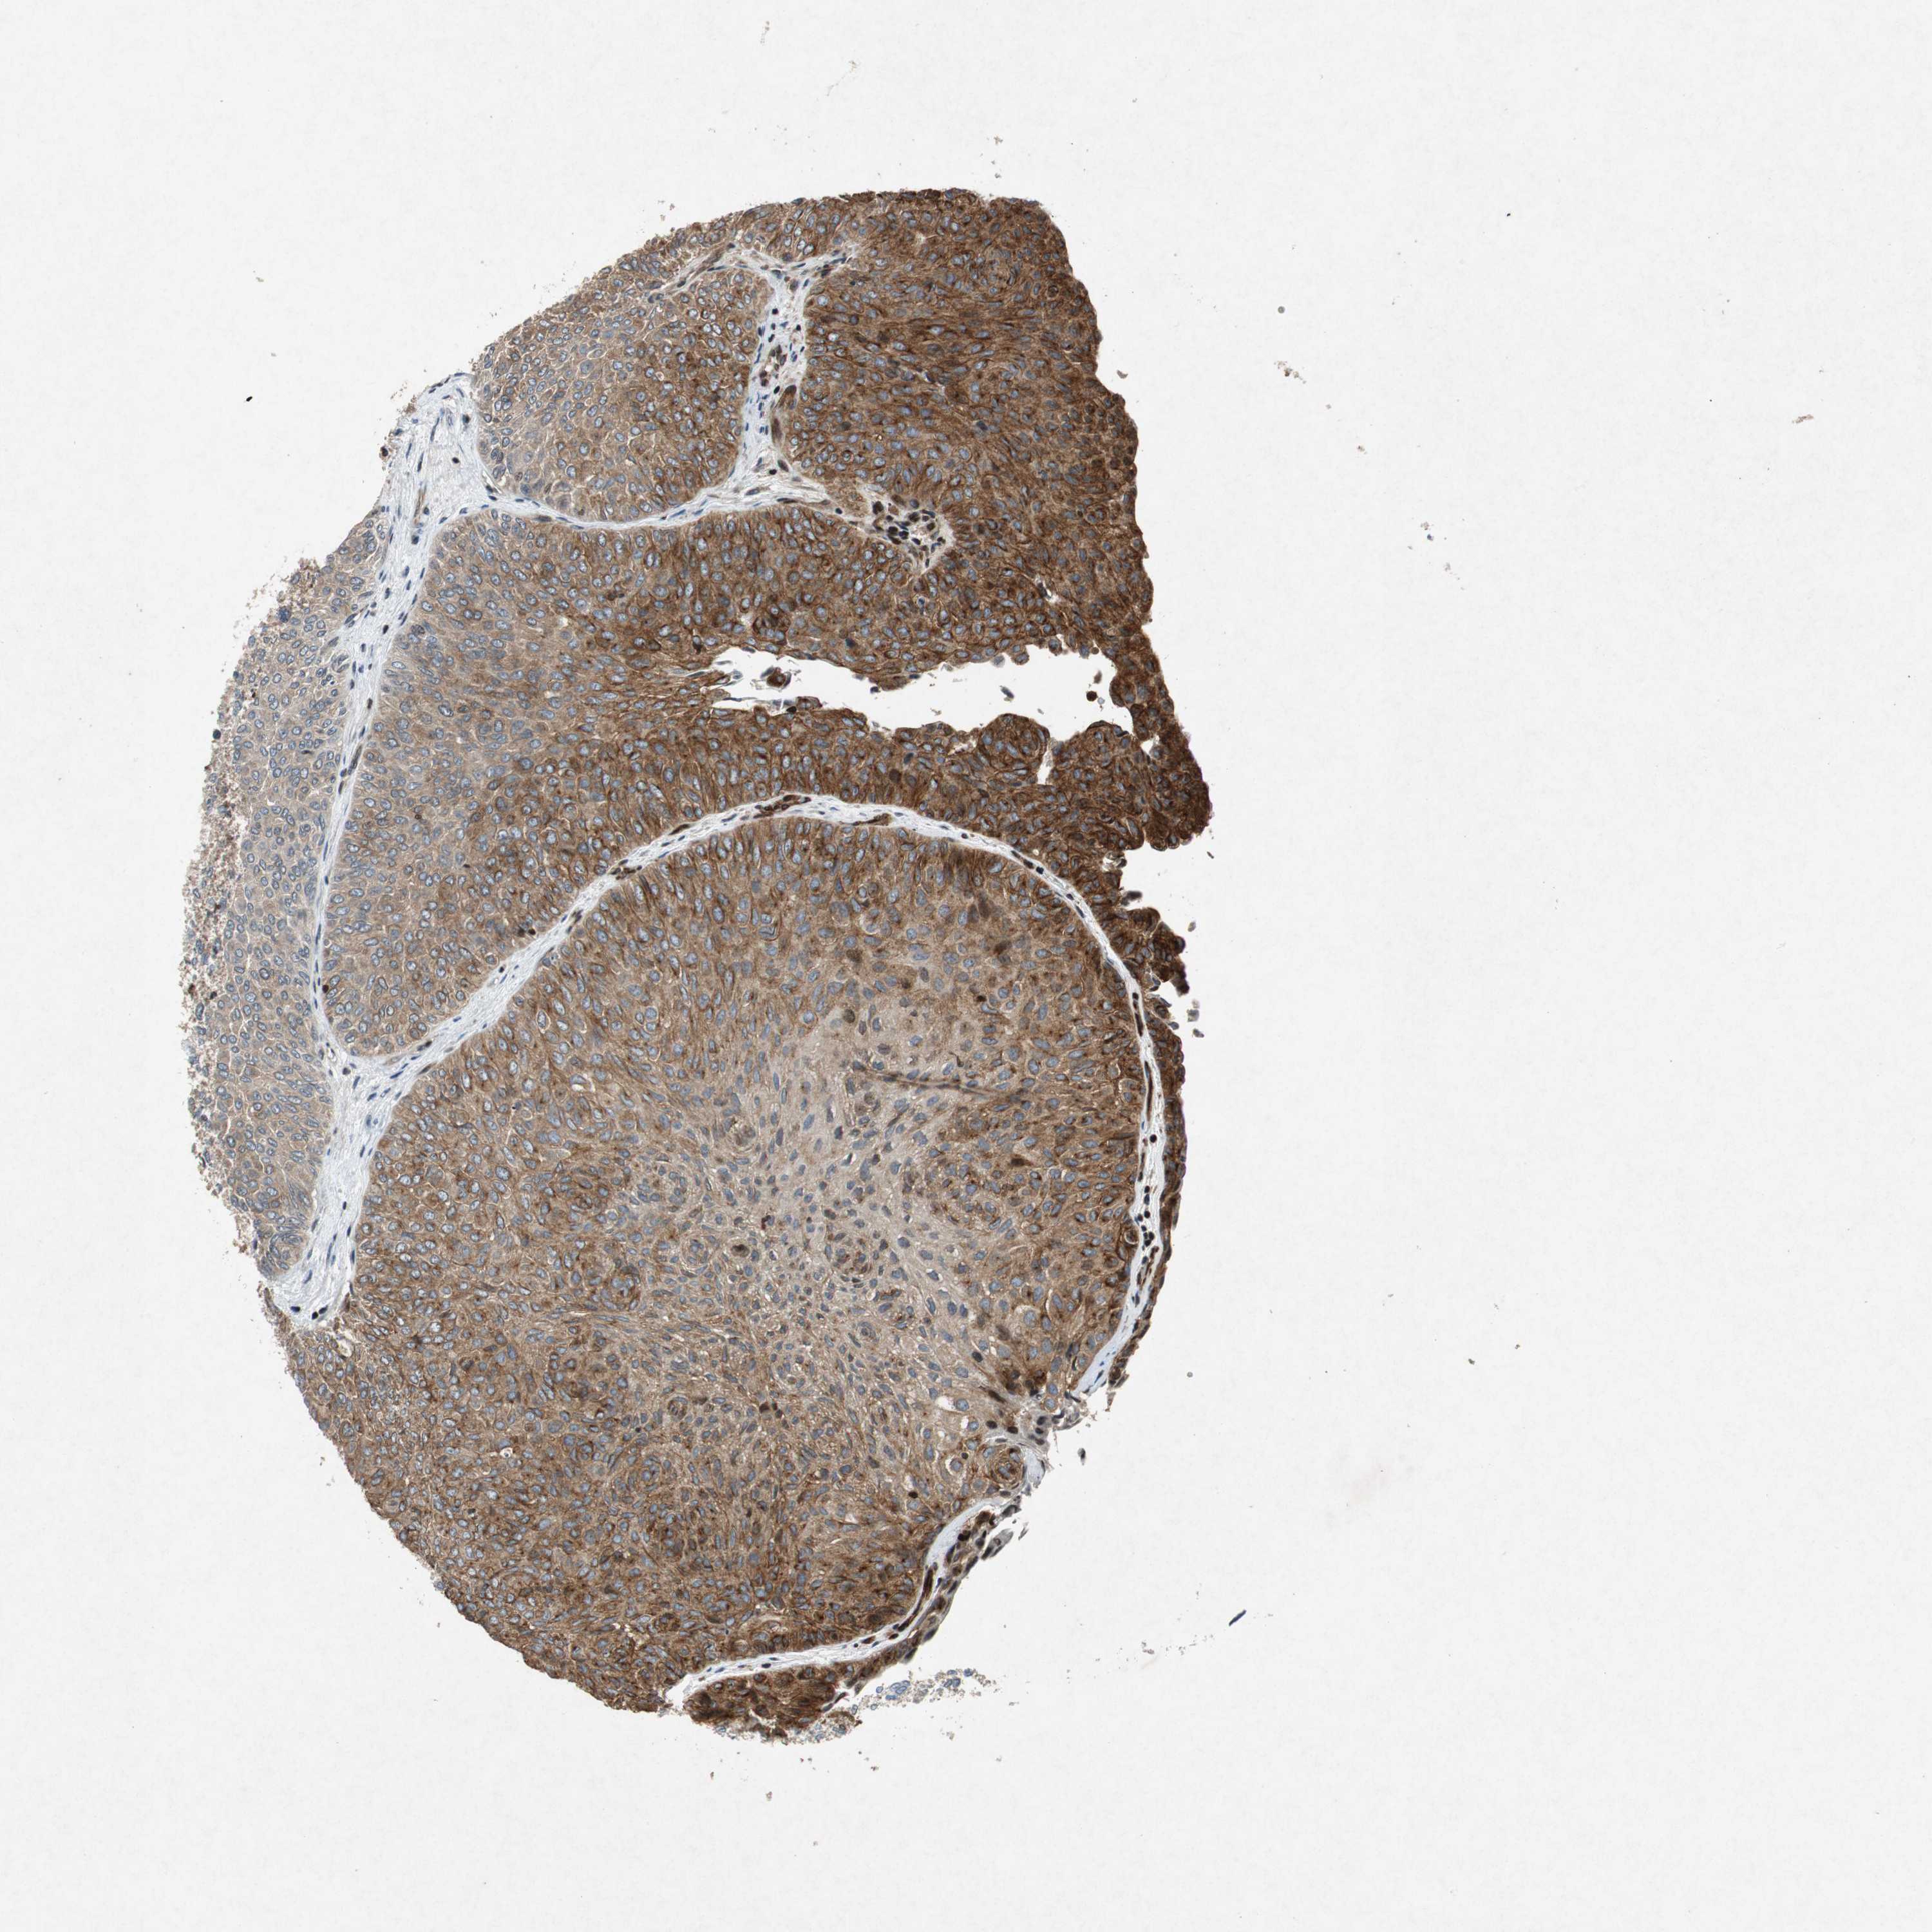

UROTHELIAL CANCER - Protein expressioni

A mouse-over function shows sample information and annotation data. Click on an image to view it in a full screen mode. Samples can be filtered based on level of antibody staining by selecting one or several of the following categories: high, medium, low and not detected. The assay and annotation is described here.

Note that samples used for immunohistochemistry by the Human Protein Atlas do not correspond to samples in the TCGA dataset.

Antibody stainingi

Antibody staining in the annotated cell types in the current human tissue is reported as not detected, low, medium, or high, based on conventional immunohistochemistry profiling in selected tissues. This score is based on the combination of the staining intensity and fraction of stained cells.

Each image is clickable and will lead to virtual microscopy that enables deeper exploration of all samples and also displays staining intensity scores, fraction scores and subcellular localization as well as patient and tissue information for each sample.

HPA039247

HPA043684

HPA063394

CAB004621

CAB005887

Staining

High

Medium

Low

Not detected

Intensity

Strong

Moderate

Weak

Negative

Quantity

>75%

75%-25%

<25%

None

Location

Nuclear

Cytoplasmic/membranous

Cytoplasmic/membranous,nuclear

Urothelial carcinoma, High grade

Urothelial carcinoma, Low grade